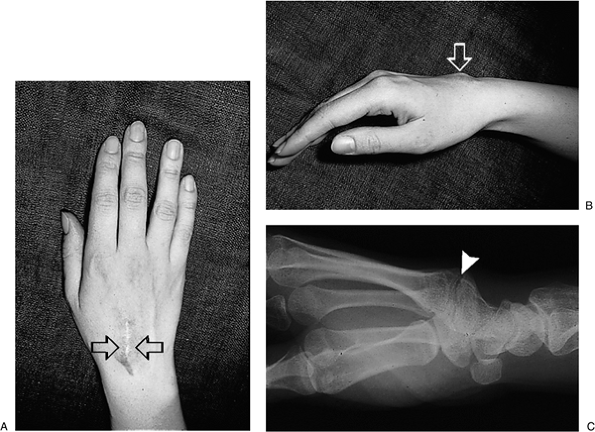

Figure 3-8 The carpal boss is often mistaken for a ganglion cyst. (A–B) Prominent mass and scar (arrows) following an attempted removal of a “ganglion.” (C) A radiograph clearly demonstrates the true nature of this mass.

|